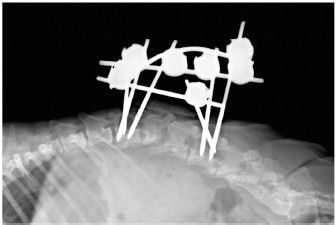

The subluxacion was reduced manually and stabilized using a bilateral and biplanar ESSF. A total of six 2.5mm positive-partially-threaded pins, eight Meynard clamps and three connecting rods were implanted. The positive-partially-threaded pins were inserted in the vertebral bodies of L1 and L4, avoiding contact with the affected vertebrae. Immediate post-operative radiographs were obtained confirming reduced subluxation and realigned vertebrae (Fig. 3).

Fig. 3. Lateral (A) and dorso-ventral (B) postoperative radiograph of the lumbar spine showing the bilateral and biplanar external spinal skeletal fixator after curettage and manual reduction of the L2–L3 subluxation.